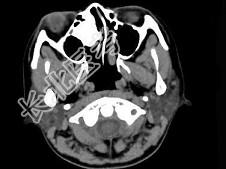

- 多项选择题女,18岁, 眼球轻度突出、眼痛、流泪近半年,CT扫描如图所示, 正确的描述或诊断是 ( )

A、右侧筛窦内见致密骨化影,鼻中隔向左偏

B、致密肿块影向右侧眼眶内突出,右眼内直肌受压

C、筛窦壁及鼻中隔未见骨质破坏

D、副鼻窦(筛窦)内骨瘤

E、副鼻窦(筛窦)内软骨瘤